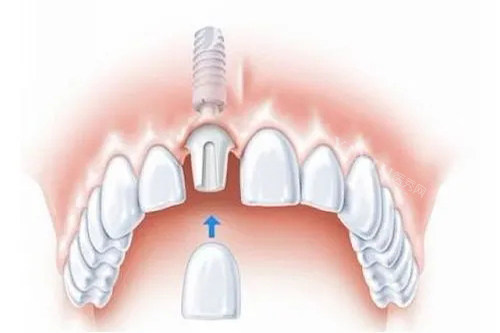

All-on-4 方案是一种较高的全口种植技术,需要植入 4 颗种植体就能支撑起一整排牙齿。其中,两颗前牙区种植体垂直植入,后牙区两颗种植体呈倾斜角度植入。这种设计巧妙利用力学原理,在骨量不足的情况下,可避开上颌窦、下颌神经管等危险区域,减少植骨需求,同时为牙桥提供稳定支撑,实现即刻负重,大大缩短患者缺牙时间,术后短时间内就能修复部分咀嚼功能。